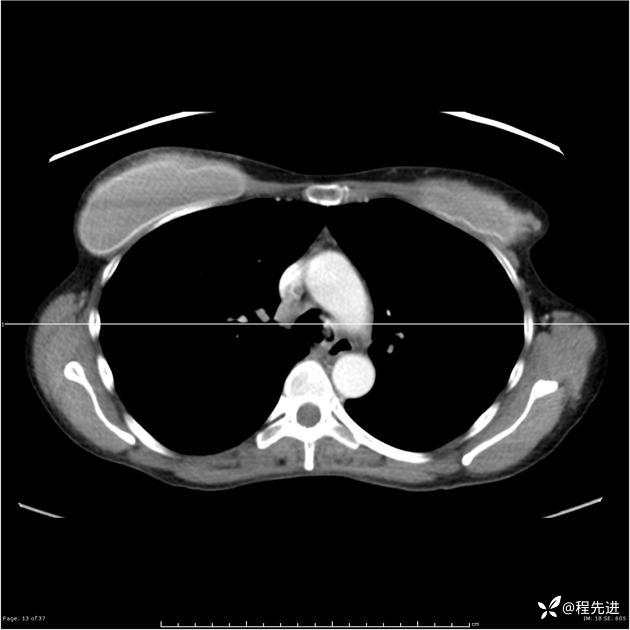

病例女,53岁,气管、左主支气管、下叶支气管内结节,乳头状瘤?期待你的精彩解读

女,53岁

乳头状瘤?